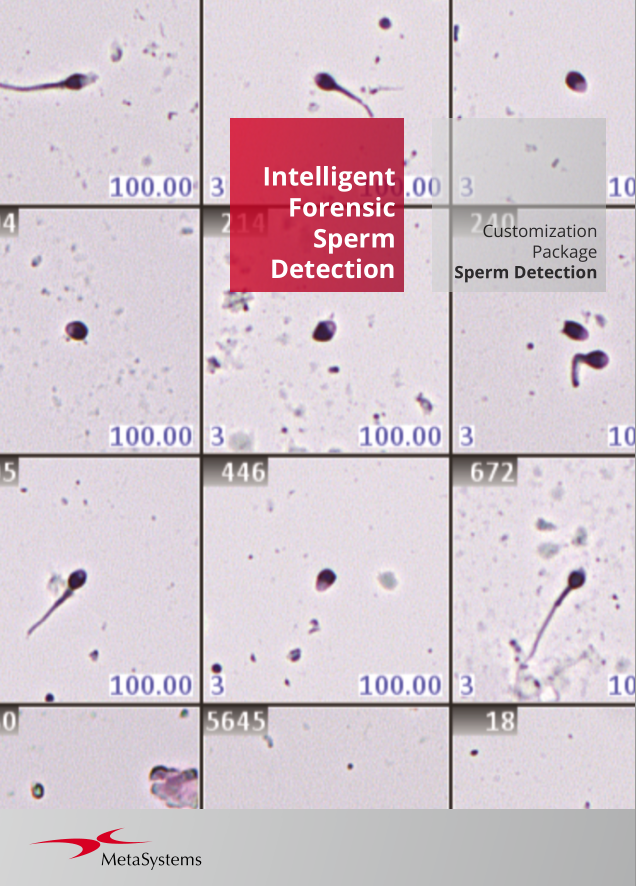

Utilizing the Metafer software, imaging systems scan specimens of diverse sizes, employ various contrasting methods and magnifications, and identify, classify, and enumerate cells or other objects. Metafer's modularity and flexible architecture make it proficient in assisting users from various fields with their specific imaging tasks.

Given the variability of each microscopic sample, automated imaging demands flexibility. Metafer's distinctive concept provides an effective solution: user-trainable classifiers accurately establish imaging standards, and by selecting the relevant classifier, the integrated scanning system swiftly transitions to the next task.